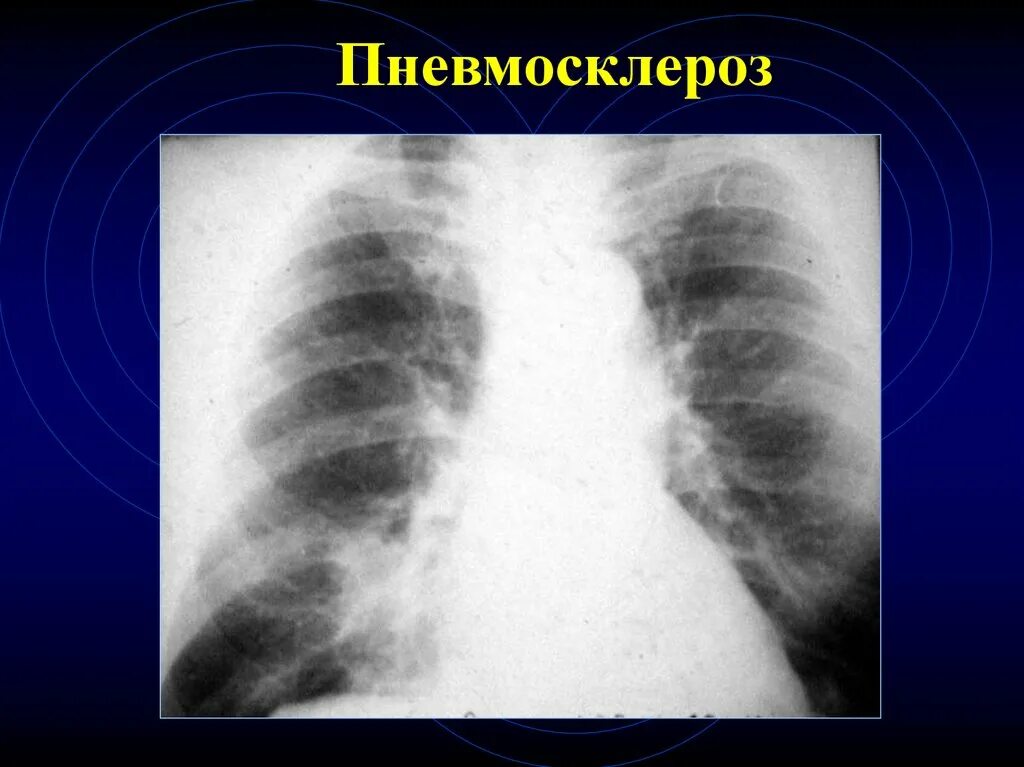

Локальный пневмосклероз легких